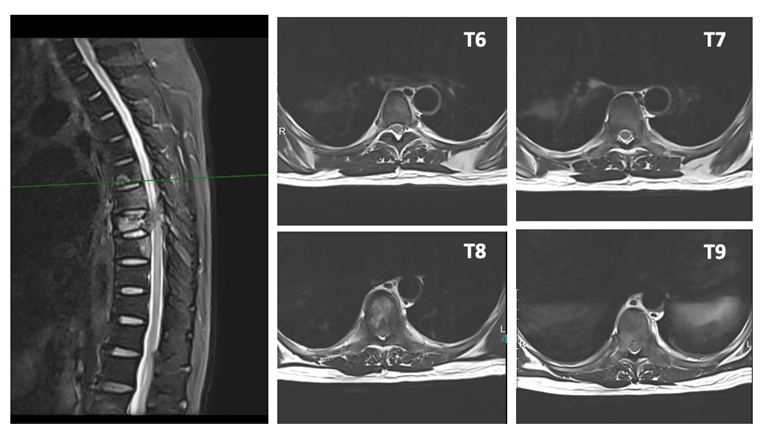

患者男性,62岁,半年前无明显诱因出现胸背部剧烈疼痛,伴下肢无力,严重影响了正常生活。就诊福建当地医院,胸部CT示:右肺下叶前基底段占位,右肺上叶后段类结节样影;T6-9椎体及部分附件多发骨质破坏。骨显像结果示:T6-9椎体显像剂摄取增高,考虑骨转移可能。遂于当地医院行肺部穿刺:(右下叶外基底段活检)结合免疫组化结果倾向腺癌。患者为行进一步治疗,至我院门诊收入病房。

1.T6-9胸椎继发恶性肿瘤(VAS 8分,SINS 11分, ESCC 1c,Tomita 6分,改良Tokuhashi 5分 )

精准手术方案:后路减压固定+分离手术+病灶射频消融。患者为肺癌晚期,经影像学证实T6-9椎体呈现不同程度的骨质破坏。此次手术方案考虑到多个椎体的不同类型及不同程度的骨质破坏,特别是胸椎T8伴有压缩性骨折且侵犯椎管。通过仔细全面的术前评估,我们为患者制定了个性化的手术方案,对于T6、T7和T9椎体,采用了射频消融技术,精准靶向骨转移病灶,有效地控制了局部肿瘤进展,同时减少了不必要的组织损伤。对于T8椎体,考虑到压缩性骨折及椎管侵犯,我们进行了后路减压固定+分离手术,减轻了神经压迫,恢复了椎体稳定性,并配合椎体病灶消融,以确保治疗效果的最大化。这种精细化的手术方案,不仅充分处理了病灶,还最大程度减少了手术创伤,为患者提供了更为安全的治疗选择,术后恢复良好。

术后半年,患者按期进行了复查,胸椎的局部控制效果好,未见新的病灶出现,T8椎管未见明显狭窄,患者的疼痛症状持续缓解(VAS 3分)。更令人振奋的是,肺部原发病灶也有明显缩小,肿瘤负担大大减轻。患者表示,术后的疼痛得到了有效缓解,能够恢复正常的生活和工作,这使他重新找到了生活的希望。